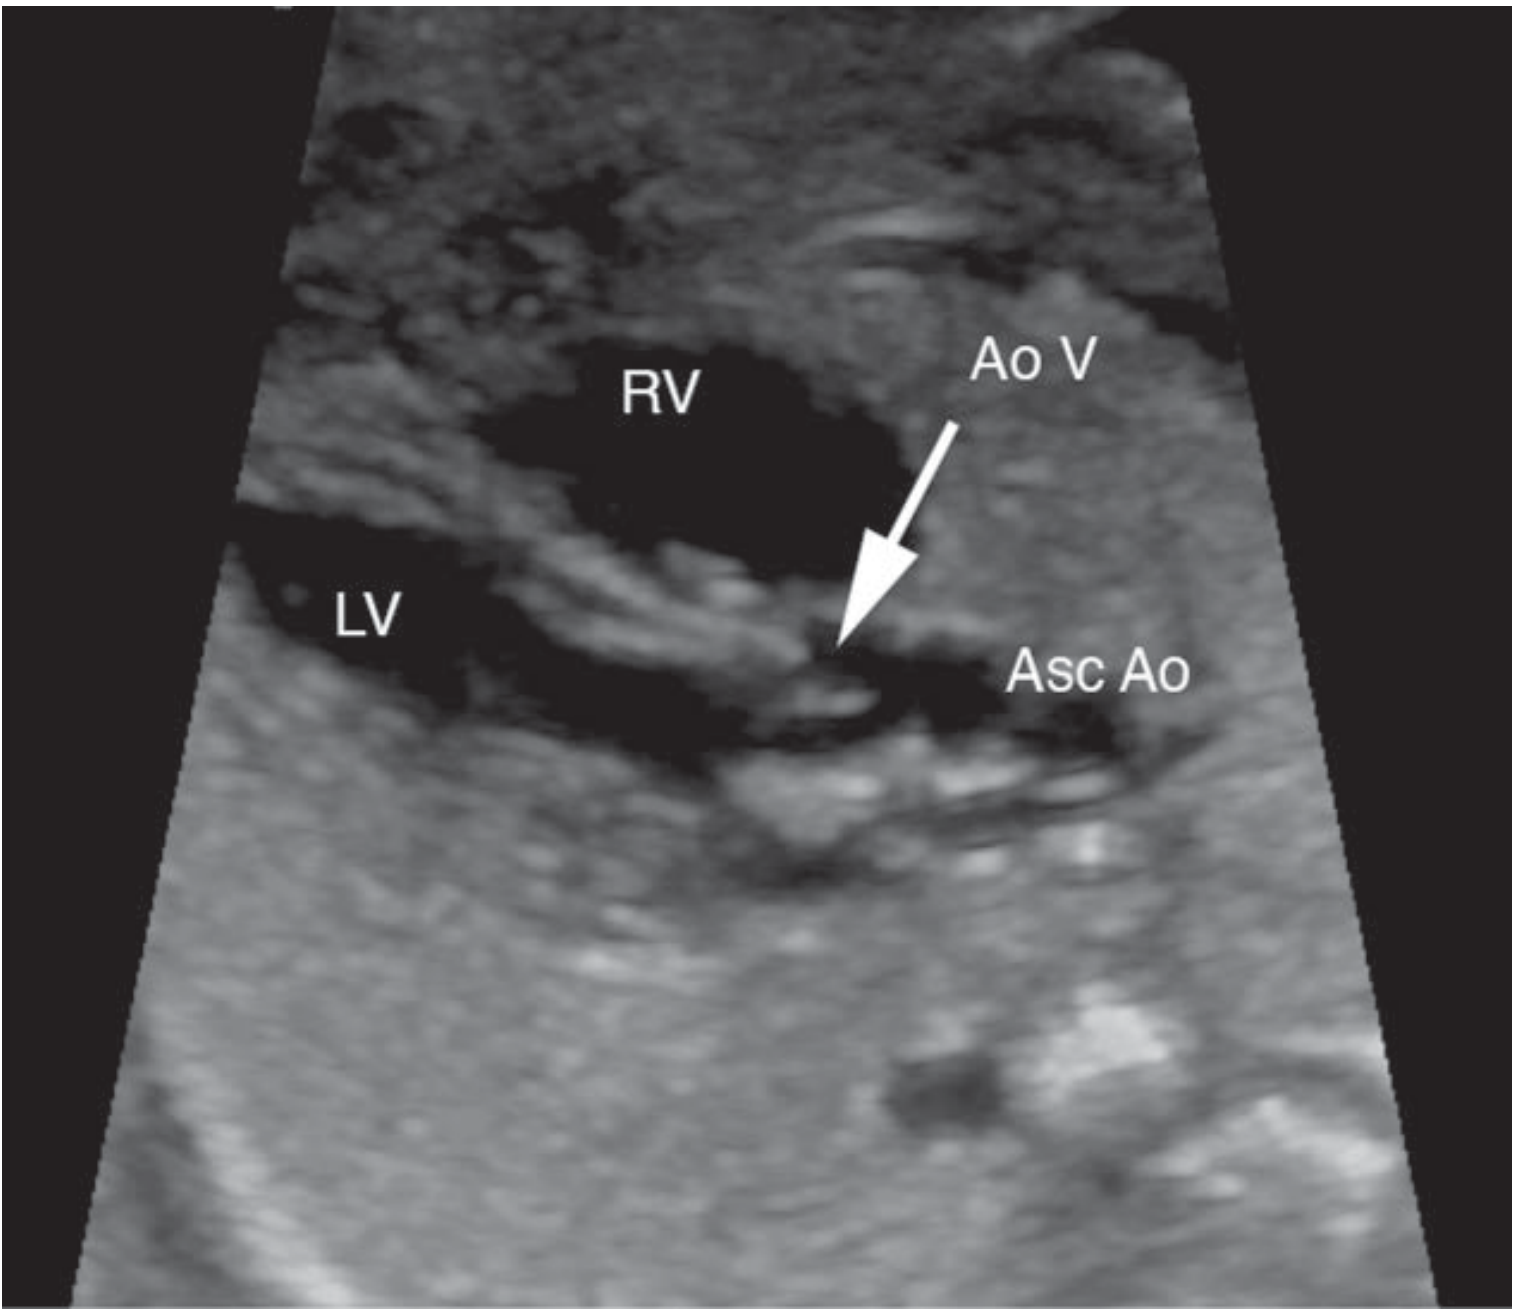

• Left and right ventricular outflow tracts

Left ventricular outflow tract

Figure: Left ventricular outflow tract